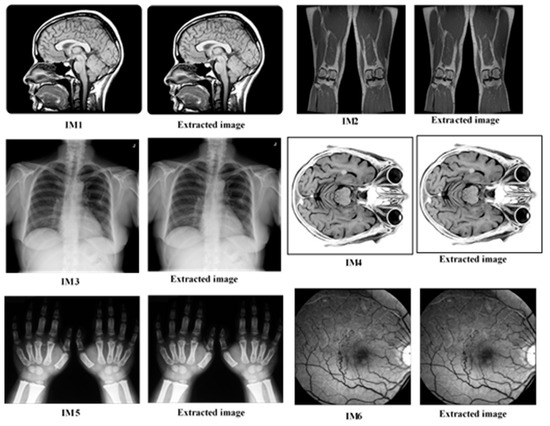

Our proposed plan was applied to six DICOM grayscale images (IM1–6). The results are shown in Table 2, and the original images (pre-encrypted and sent to the cloud) along with the validated images (after downloading and decoding) can be seen in Figure 10. Using the human optical system to detect differences between the original images and the relevant reliable images (Figure 13), it is no one could detect any difference between them; therefore, the proposed system has the ability to encode and decode the original DICOM grayscale without any noticeable distortion. The results in Table 1 show that the NC rate was equal to 1 and the BER was 0 for all test images. This means that the bit stream sequence extracted from the image on the receiver side matched the bit stream of the image at the owner side.

Figure 13.

The original and authenticated grayscale medical test images.

These results demonstrate that the proposed technology is safe and fast. The original images could be restored by the receiver without any distortion or manipulation, ensuring the integrity of the images due to the defragmentation function, which can be extracted without errors. To verify that the technology was able to detect whether the image was incomplete, documented, corrupted or manipulated, the sender set one pixel of image authentication and returned it to the cloud, where the receiver detects the modification through the proposed technique and sent a message to the owner that the image was no longer authenticated.

In Table 1, show the minimum SNR was 47.90 dB, and the maximum value of the MSE was 0.184, indicate that the SNR and MSE has a very low fixed value, and that the encryption and decryption process did not affect the quality of the original images. The PSNR had large fixed values: the minimum value was 53.89 dB, while the high value was 61.01 dB and the NC of all images was equal to 1. The empirical results applied to the medical images in grayscale (Figure 10) indicate that corruption of the encoded images associated with the cloud was low when downloading and decrypting them (while ensuring the speed) in comparison with the original images on the side of the receiver.